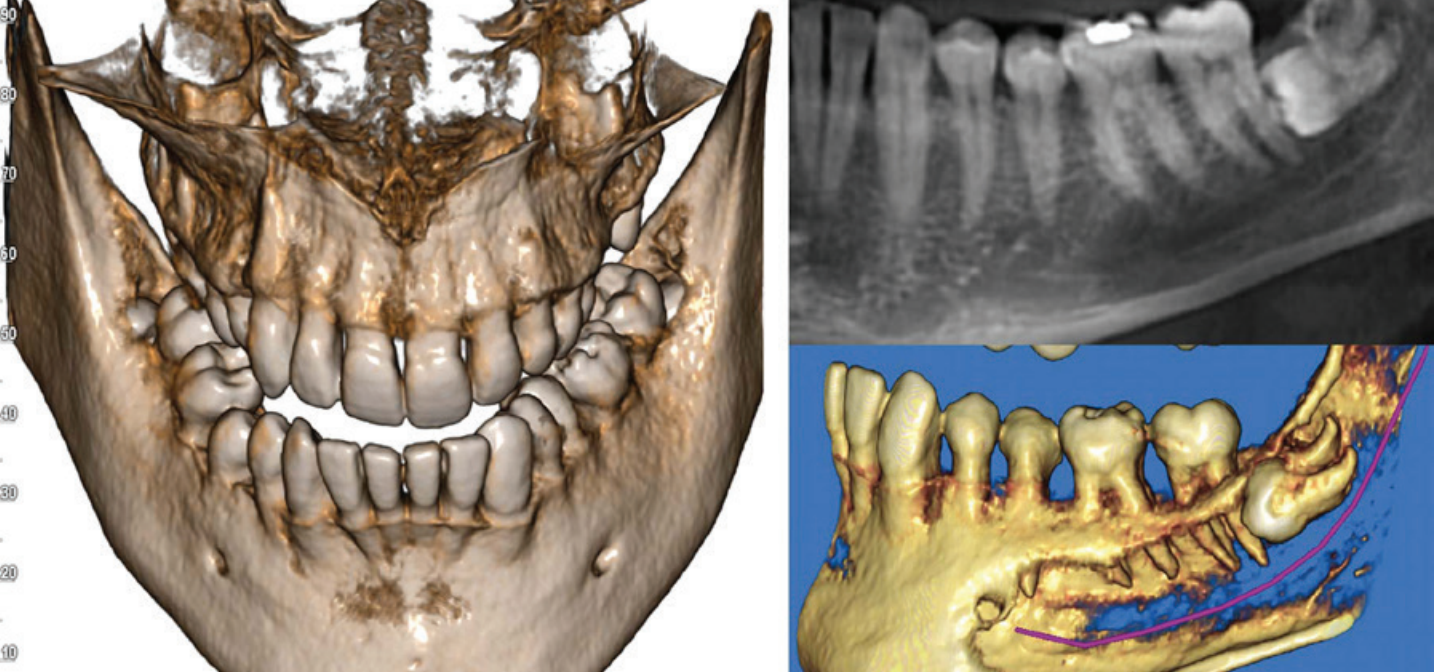

10x10 fov alanı üçüncü molar kökler ve sinüs tabanları dahil, çevresindeki anatomik özelliklerin yüksek doğrulukta taranması, doğru teşhis ve iyileştirilmiş tedavi planlaması için yararlıdır. X5 10 x 10cm fov alanını 80 μm luk detaylarla vermektedir.

Endodontik değerlendirmeler için sadece ilgili bölgedeki ayrıntılı teşhisler yapılabilmektedir. 2D görüntülerden çok daha derinlemesine gömülü dişler arasındaki ilişkilerin neredeyse bir periapikal dozunda incelenmesi sağlar.

IRYS ile 2D/3D TARAMALARININ YÖNETİMİ 2D ve 3D görüntülerin yönetimi tek bir yazılım üzerinden yürütülür. Çoklu Masaüstü sistemi, 2 boyutlu ve 3 boyutlu görünümler arasında hızlı gezinme mümkündür. Yüksek kaliteli teşhisler yapmak ve hasta ile hızlı bir şekilde iletişim kurmak için ihtiyaç olabilecek her şey IRYS yazılımdadır.

İmplant bölgesini çevreleyen anatomik yapılar hakkında bilgi verir. Kemik kalitesinin değerlendirmesi ve gelişmiş IRYS yazılım özelliğiyle cerrahî prosedürlerin, ameliyat sonrası iyileşme sürelerinin en iyi şekilde planlanması mümkün olur. Bu özellik sayesinde geniş kapsamlı yazılımın implant kütüphanesinde bulunan implantların seçilip konumlandırılarak görüntüler üzerinde planlama yapılabilir.